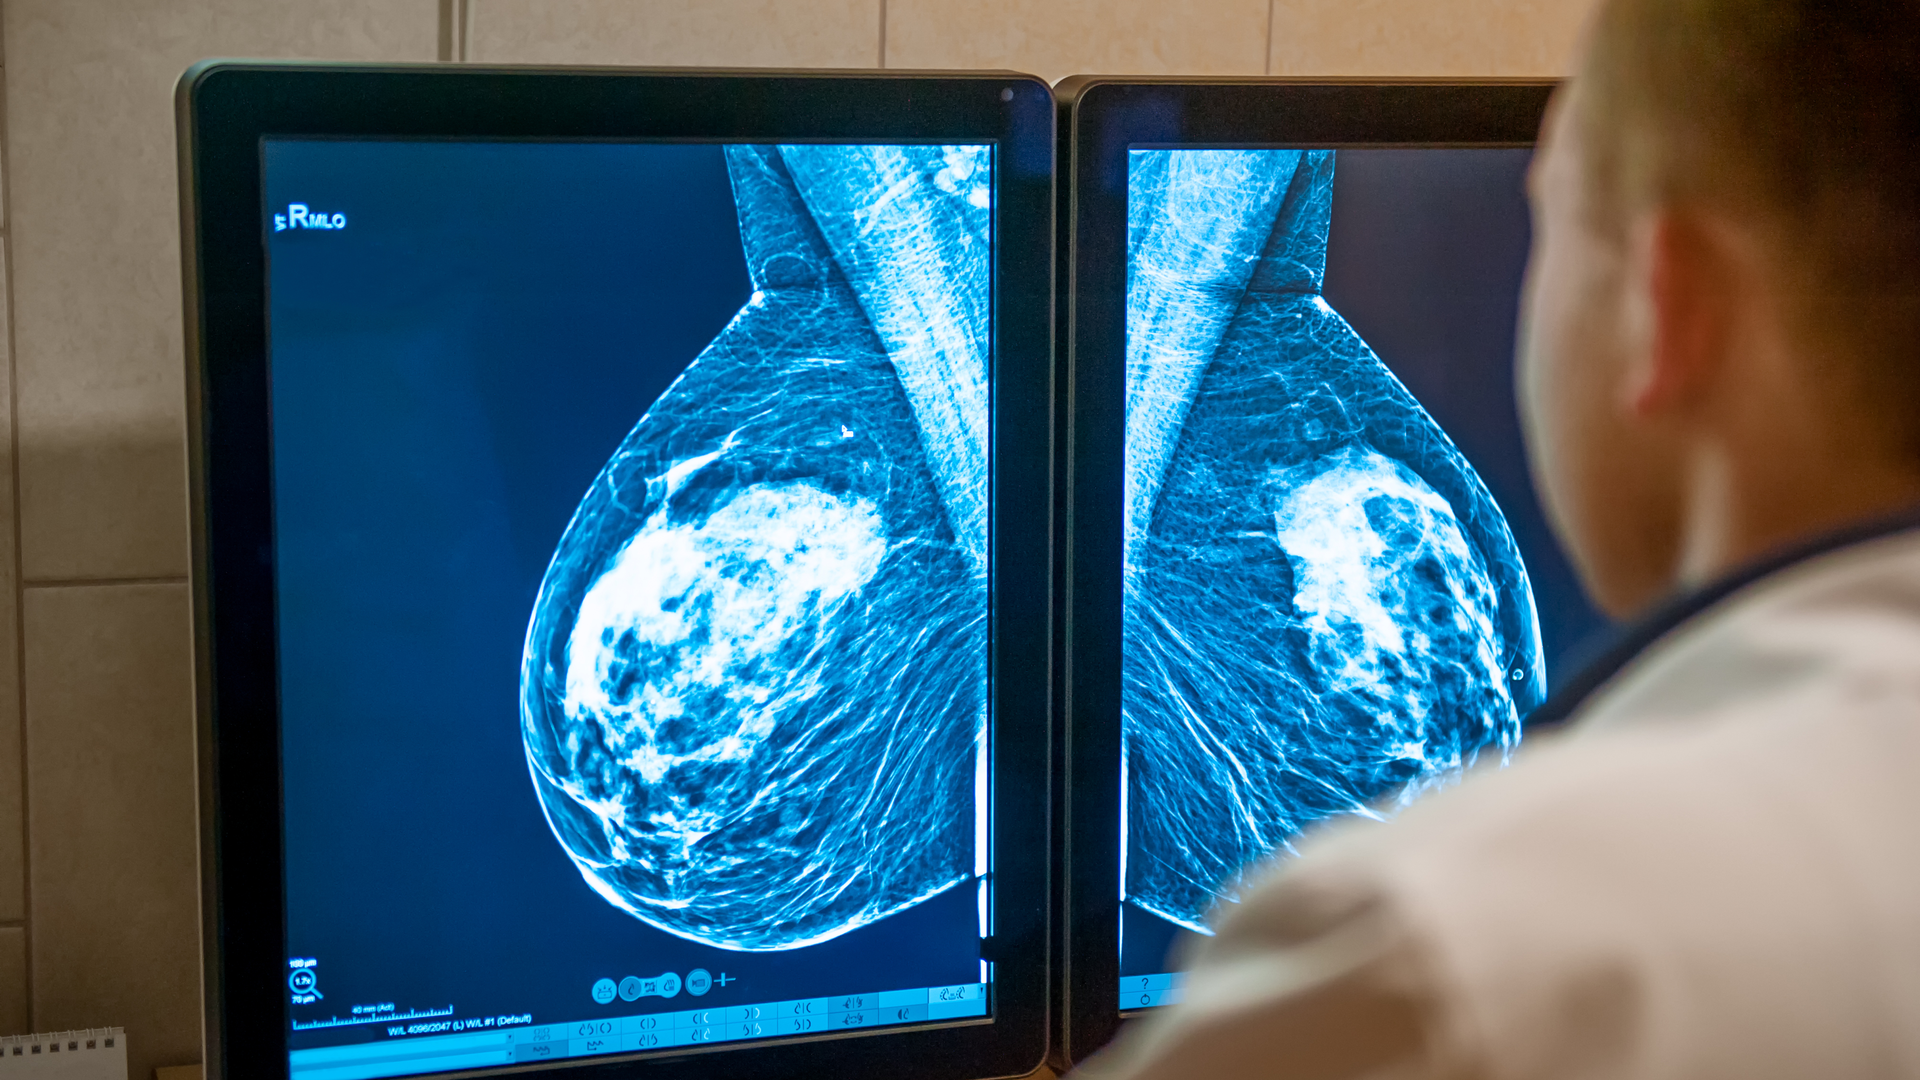

When doctors read mammograms, they assess breast density along with signs of cancer, comparing a woman’s previous mammograms to her most recent one to look for worrisome changes. But some changes are difficult to detect by eye.

Since breast cancer rarely develops in both breasts at the same time, Jiang analyzed the images of each breast separately. Women’s breasts normally become less dense as they age, but Jiang discovered that density declined significantly more slowly in the breasts that later developed cancer than in those that did not.

“In the future, I think we can use a woman’s past history of density, plus her current density estimate, to better understand her risk level,” Jiang said. “We may even be able to determine which breast will be affected, because the density signal is strongest in the breast that goes on to develop cancer. Many women already get regular mammograms, so the data on density in each breast is already being collected. We just need to use the data more effectively.”